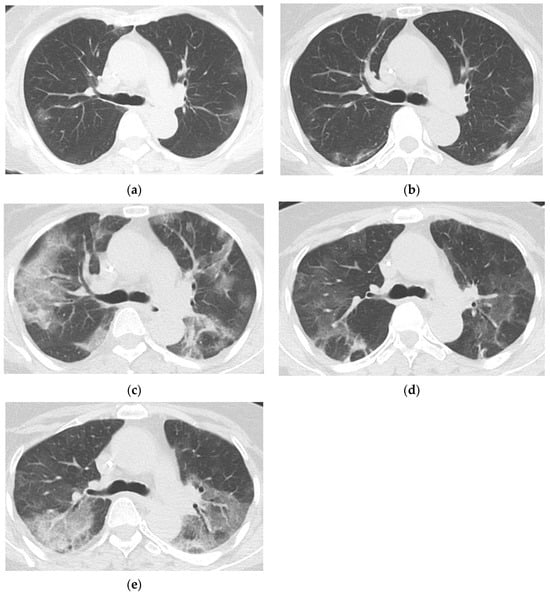

3.3. Baseline and Follow-Up Chest CT Findings

4. Discussion